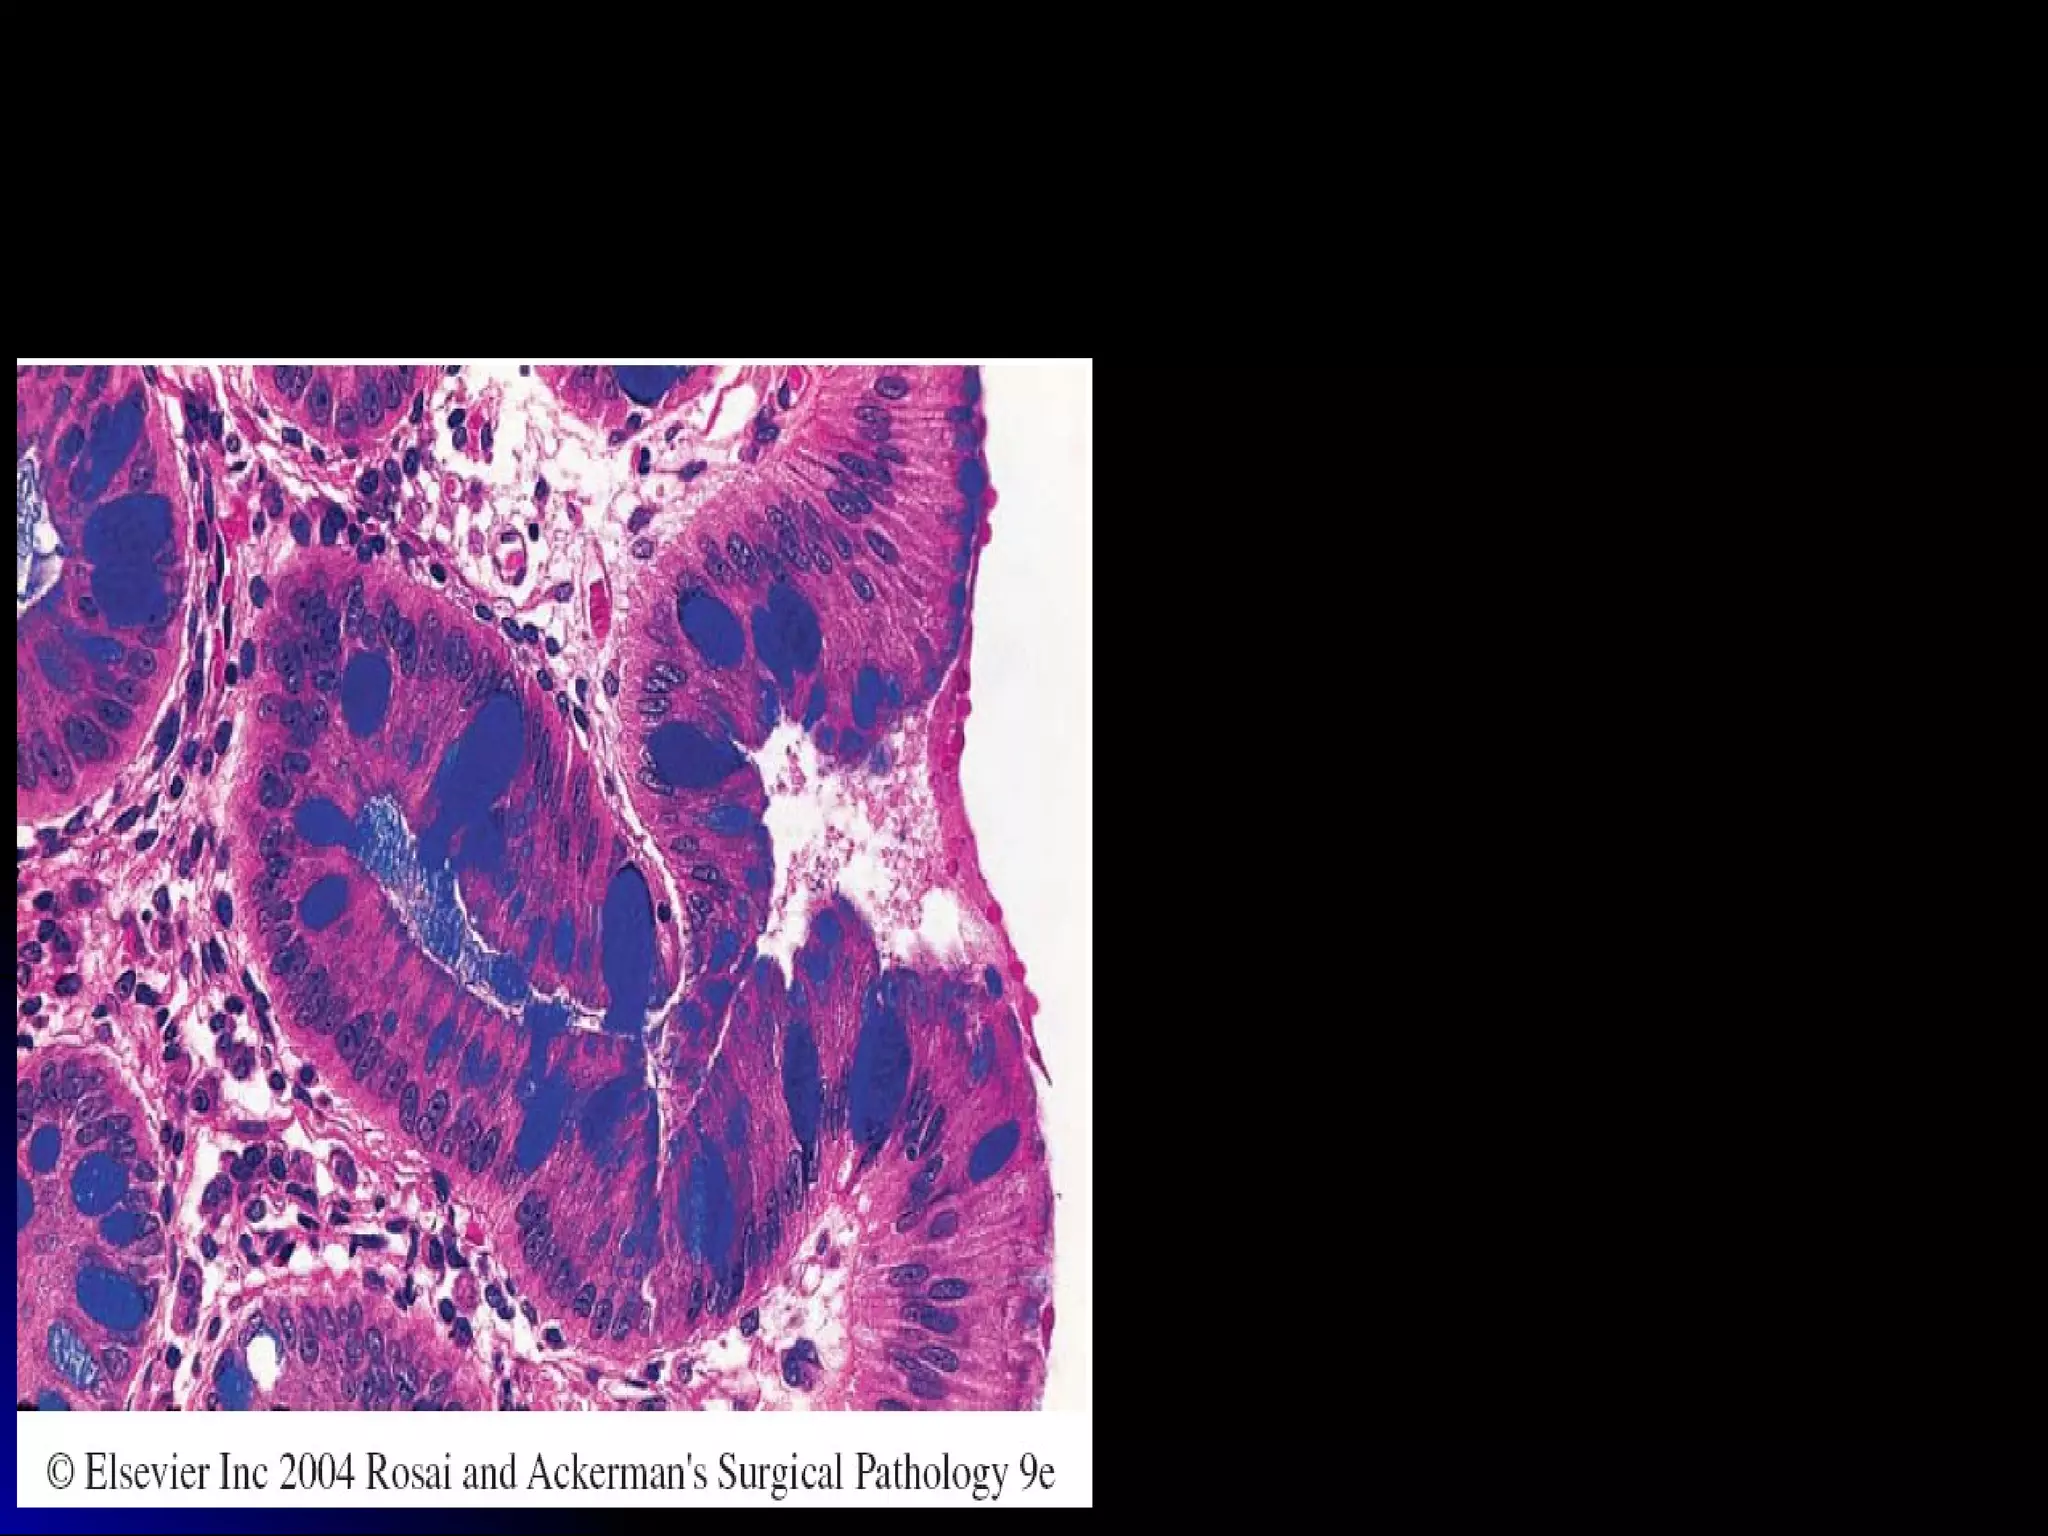

Carcinoma of stomachCarcinoma of stomach

 IntestinalIntestinal

adenocarcinoma &adenocarcinoma &

diffuse type, signetdiffuse type, signet

ring cell ca.ring cell ca.